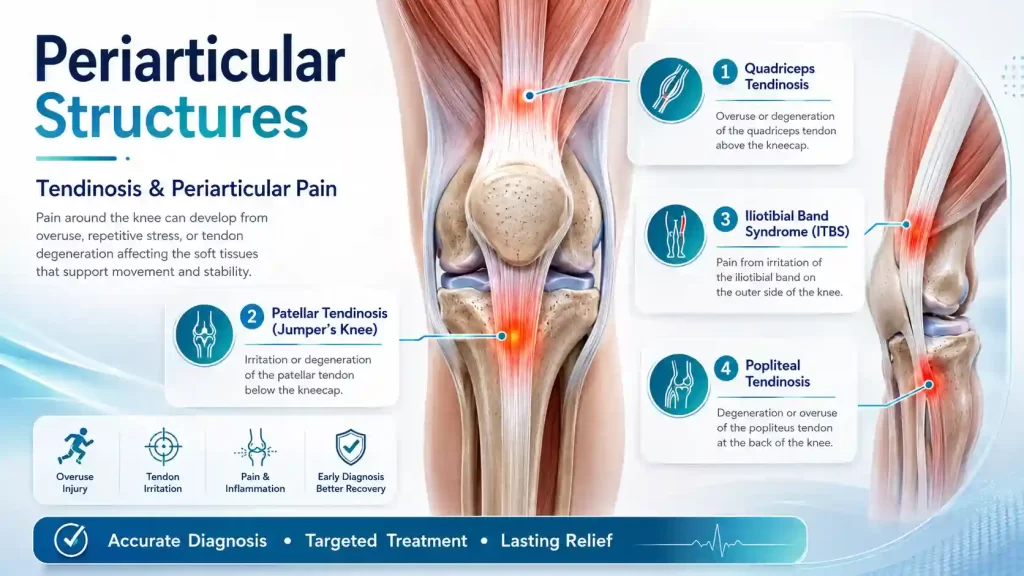

The patellar tendon connects the kneecap to the shin bone and is put under enormous stress during jumping, landing, and kicking. Repetitive overload causes degenerative changes (tendinosis) rather than true inflammation the tendon becomes thickened, disorganised, and painful. PRP injected precisely into the tendon under ultrasound guidance stimulates a healing response that physiotherapy alone cannot achieve.

Similar degenerative changes in the quadriceps tendon (above the patella) present as anterior knee pain, particularly in older athletes and individuals with a high BMI. Eccentric loading programmes combined with PRP or prolotherapy yield excellent results.

A friction syndrome causing lateral knee pain in runners the iliotibial band (a thick band of fascia running down the outer thigh) repeatedly rubs over the lateral femoral condyle. Ultrasound-guided injection at the point of impingement, combined with targeted hip strengthening, resolves the condition in most cases.

The popliteus muscle a small but vital stabiliser at the back of the knee can develop tendinosis, producing postero-lateral knee pain, often confused with a meniscal tear. Ultrasound assessment and targeted PRP injection are highly specific for this underdiagnosed condition.

Tendinosis vs Tendinitis: True inflammation (tendinitis) is short-lived. Most chronic tendon pain is actually tendinosis — degenerative disorganisation without inflammation. This distinction matters enormously because corticosteroids, which suppress inflammation, can weaken and even rupture a degenerated tendon. PRP and prolotherapy are therefore far safer and more effective long-term choices.